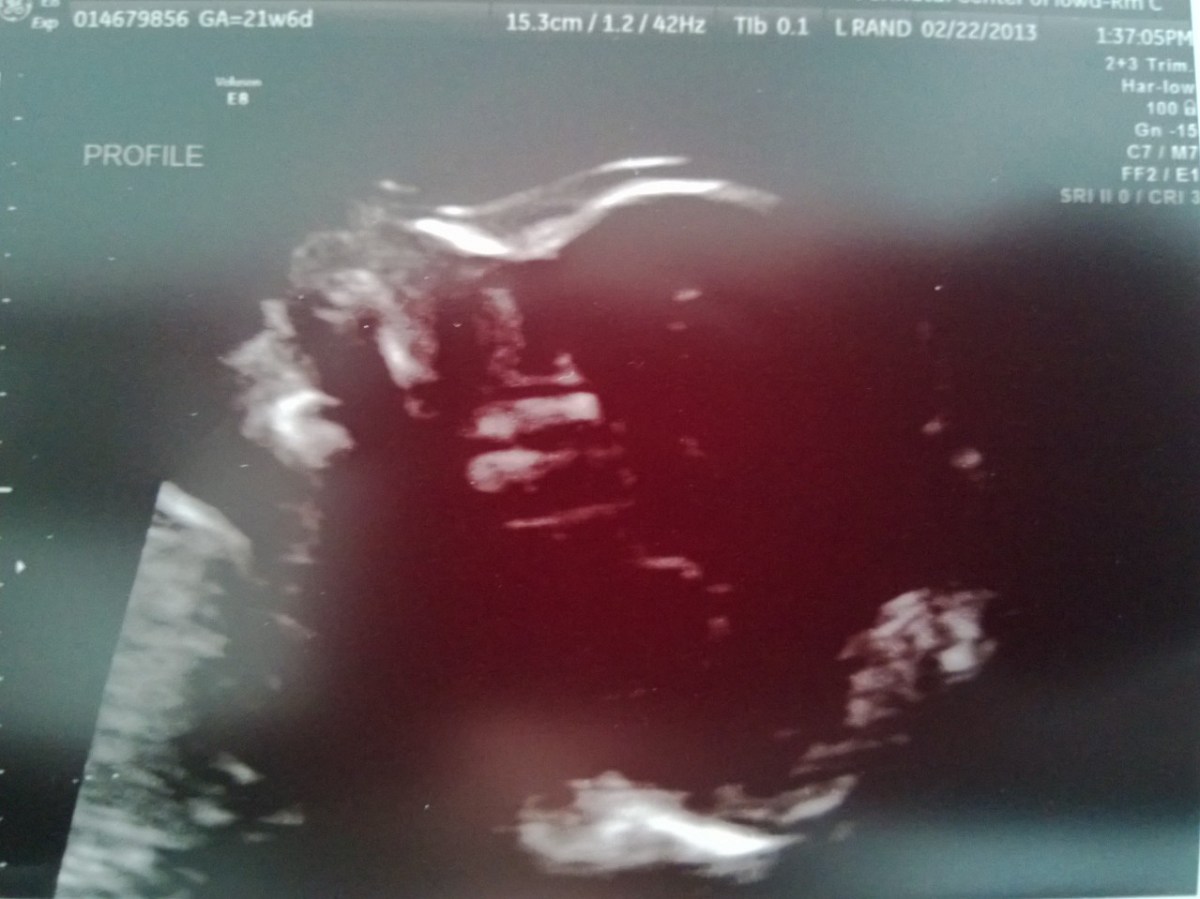

WP_20130222_012 February 22, 2013 by Courtney Leave a comment ← Previous Image Next Image → 21w6d Like Loading...